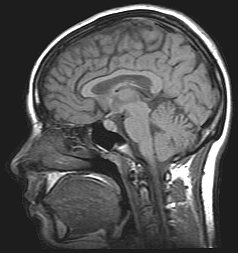

Изображение головного мозга человека с внутричерепной гипертензией по результатам МРТ | |